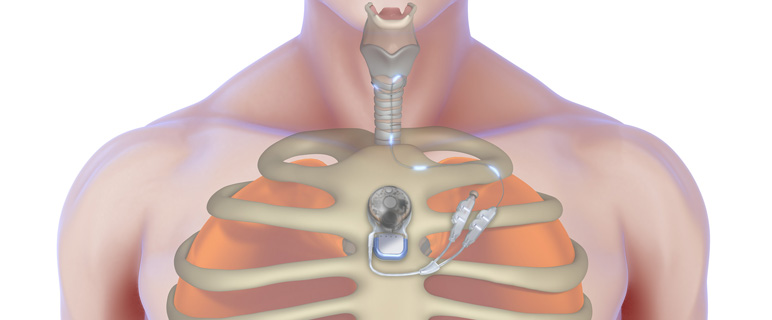

Prof. Riechelmann: Der Kehlkopfschrittmacher stimuliert die Nerven des Öffnermuskels innerhalb des Kehlkopfs, sodass die Patient:innen frei durchatmen können. Das System besteht aus einem Implantat, das direkt unter der Haut am Brustbein eingesetzt wird und einer Elektrode, die von diesem Implantat im Körper bis zum Kehlkopf führt. Dort wird sie mit dem Muskel verbunden. Steuerung und Energieversorgung erfolgen über einen externen Prozessor, der magnetisch am Implantat, also am Brustbein haftet. Der Prozessor gibt ein Steuersignal an das Implantat und das Implantat sendet einen Impuls an den Kontakt im Muskel, der wiederum die Stimmlippen bewegt und den Atemweg frei macht.